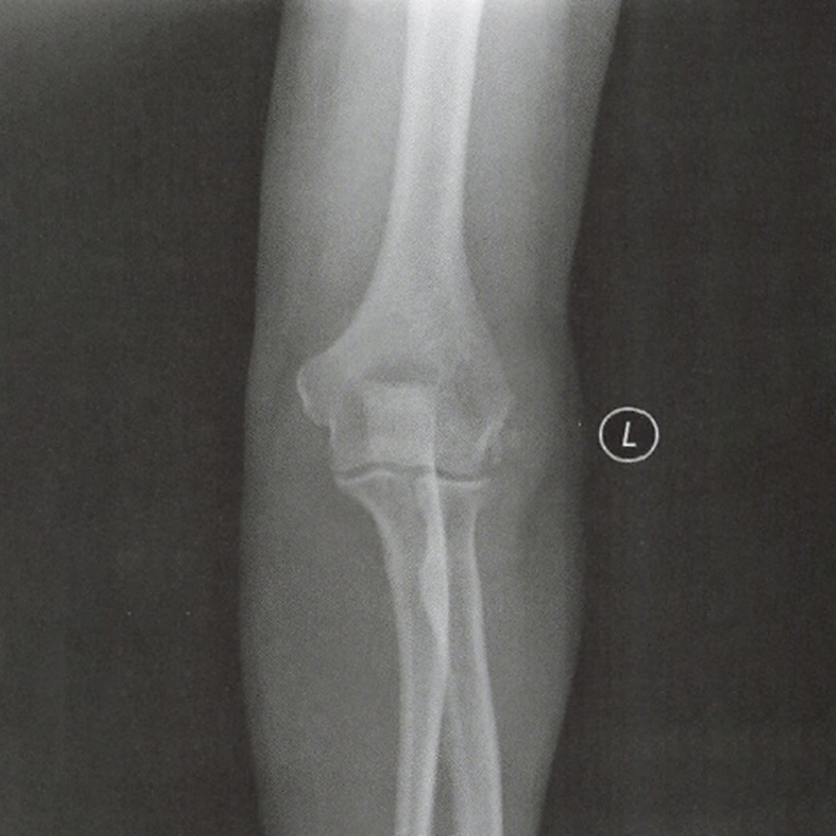

(1)X线平片常规正、侧、轴位X线平片少有异常发现,但可以排除肘关节的合并疾病,如骨关节炎时关节后外侧旋转不稳定等。偶尔会发现钙化性腱鞘炎。